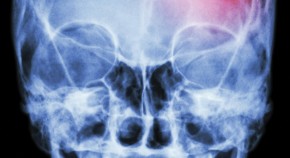

• The past year saw the 40th anniversary of the Glasgow Coma Scale, which continues to be effective for monitoring patients with traumatic brain injury. Three new clinical trials were completed, but none revealed beneficial interventions. These failures have prompted exploration of more-subtle therapy targets, novel disease classifications and collaborative research paradigms.

• David K. Menon

• Andrew I. R. Maas